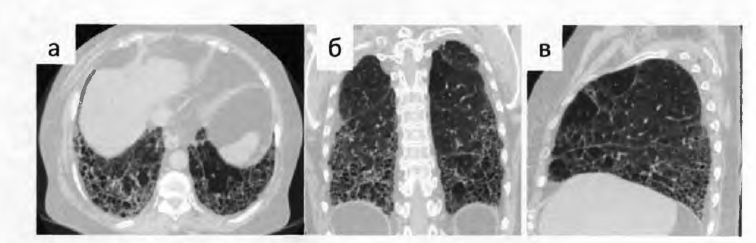

КТ ретроперитонеального фиброза: Изображения и диагностика